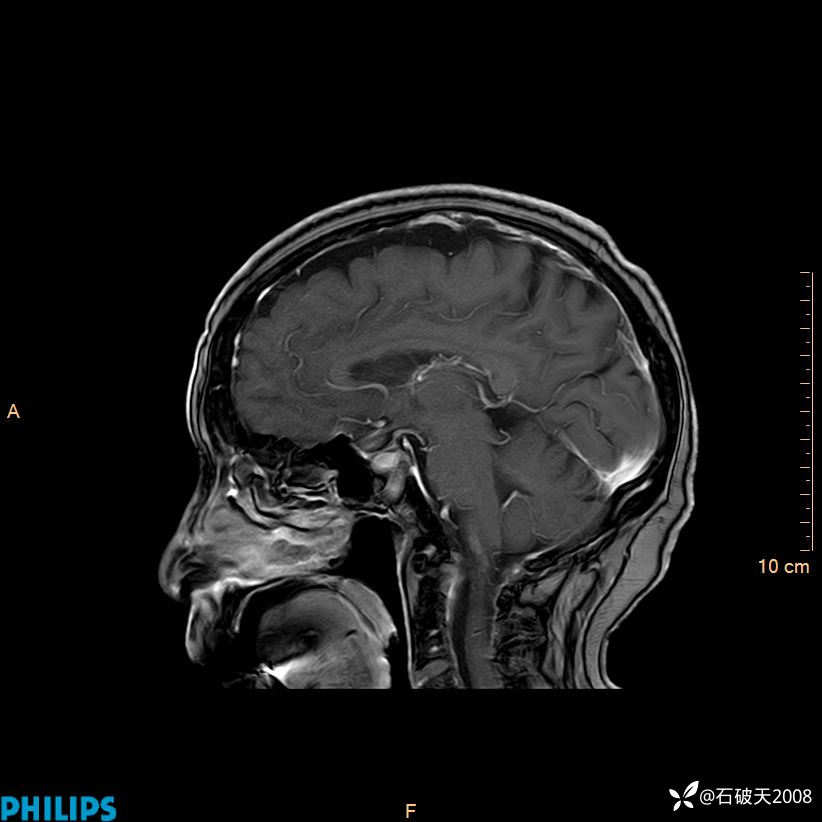

增强矢状位